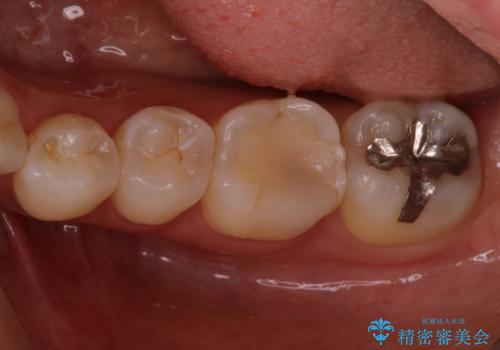

銀歯を無くしたい セラミックインレー

- 銀歯が気になるということで来院された患者様です。

セラミックでの治療を希望されたので治療をいたしました。

銀歯は長い間使用していると隙間ができて、虫歯の原因になります。

そのため適合の良いセラミックをお勧めいたします。